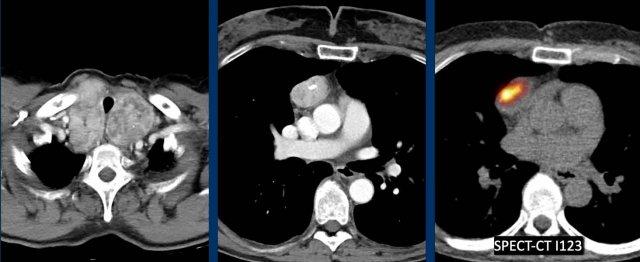

Các hình ảnh này của một bệnh nhân nữ 37 tuổi.

Bệnh nhân bị viêm phổi và hồi phục không tốt, được chỉ định chụp CT.

Hãy phân tích hình ảnh trước.

Câu hỏi: chẩn đoán có khả năng nhất là gì?

Hình ảnh

Có một khối ngấm thuốc mạnh trong khoang trước mạch máu.

Lưu ý hình ảnh tương tự như khối ngấm thuốc ở vùng tuyến giáp.

Tuyến giáp lạc chỗ có hình ảnh giống như bướu giáp.

Đôi khi có sự liên tục với tuyến giáp bình thường và đôi khi tuyến giáp bình thường không có mặt.

Có thể xác nhận chẩn đoán bằng xạ hình tuyến giáp.

Đây là một ca lâm sàng tương tự.

Có bướu giáp và một khối ngấm thuốc trong khoang trước mạch máu của trung thất.

I-123 là đồng vị phóng xạ của iốt được sử dụng để xạ hình tuyến giáp.

Trong trường hợp này, sự hấp thu được quan sát trên SPECT-CT.